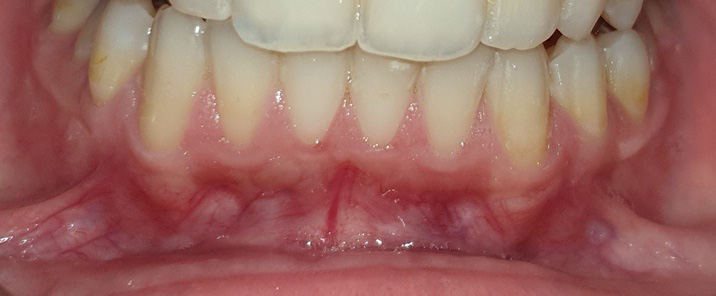

The graft was positioned in its bed and held pressed for 2 min for initial stability. At one side, the graft was stabilized using 0/5 nylon sutures (interrupted sutures to the papilla and a sling suture were placed to adapt the graft intimately to the root and periosteal bed),25 while at the other side, FGG was stabilized with the tissue adhesive (Figure 2, Figure 3, Figure 4).

As to the healing index, there were no significant differences between the 2 sites after 1 week, 2 weeks, 1 month, and 2 months. However, the healing process was completed 1 month postoperatively in the tissue adhesive group, whereas in the suture group, it lasted up to 2 months (Table 5) (Figure 5, Figure 6, Figure 7).